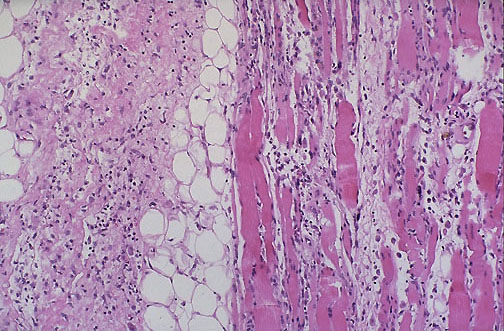

| Necrotizing fasciitis is an uncommon complication, but can be devastating because it is often infectious, with spread through soft tissue planes. Note the myonecrosis with many neutrophils extending through the muscle and soft tissues, indicative of marked acute inflammation. Surgical drainage and debridement are necessary. |